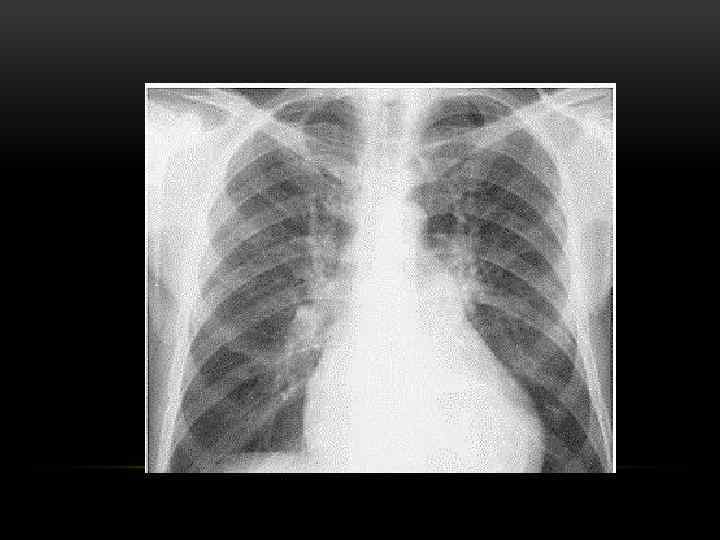

РЕНТГЕНОЛОГИЧЕСКОЕ ИССЛЕДОВАНИЕ • Задачи – исключение неопластического процесса и туберкулеза легких • При бронхитическом варианте ХОБЛ обнаруживается повышенная плотность стенок бронхов, их деформация • При эмфизематозном –оценка степени эмфизематозности легких

РЕНТГЕНОГРАФИЯ: ЭМФИЗЕМА, ЛЕГОЧНАЯ ГИПЕРТЕНЗИЯ, КАРДИОМЕГАЛИЯ • Уплощенная диафрагма • Повышенная прозрачность легких • Гипертрофия правых камер сердца